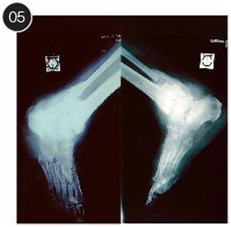

Case-1 Diabetic foot Charcot joint arthropathy with DM with CKD (Figures 1-5).

Figure 1 Pre-operative radiographic views (a,b) of a Charcot neuropathy ankle joint after an open reduction and internal fixation repair of an ankle fracture. There was a significant deformity with unstable ankle and deep infection. The patient underwent removal of internal hardware followed by primary ankle compression arthrodesis using Ilizarov fixator (c,d,e,f).